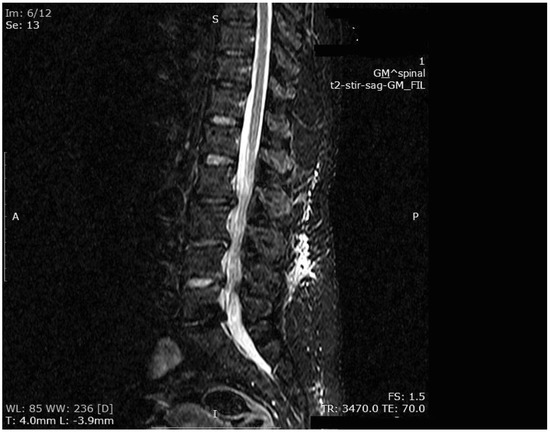

Figure 4. MR imaging T2-weighted scan showing inflammatory infiltrates in the course of pre-HBO2 treatment.

The mean number of total HBO2 sessions was 33 (±18.5) sessions. The HBO2 treatment was tolerated well by all patients except two. One patient had to receive analgesics (non-steroidal anti-inflammatories) before HBO2 sessions because she had severe back pain, and in one patient the treatment was interrupted for five days because of minor middle ear barotrauma. Improvements in clinical evaluations and laboratory findings were observed in all cases at the end of the HBO2 therapy. The mean erythrocyte sedimentation rate (ESR) value reduced from 76.1 (range, 6–129) to 45.7 (range, 5–81) mm/h, and the mean C-reactive protein (CRP) concentration reduced from 82.9 (range, 14–202) to 17.5 (range, 1–49.5) mg/L (normal limits; ESR: <20 mm/h, CRP: 0–5 mg/L). Infection resolution was adequately achieved in 12 of 13 patients on MR imaging at the end of HBO2 treatment or during the first month of follow-up (Figure 3, Figure 4 and Figure 5). There was no significant improvement in one patient. To extend the total clinical follow-up period up to three years (mean: 11 months; range, 1 month–3 years), telephone interviews were conducted to determine any recurrence of symptomatic clinical infection. No recurrence of infection, spinal instability, or deformity was seen in any patients.